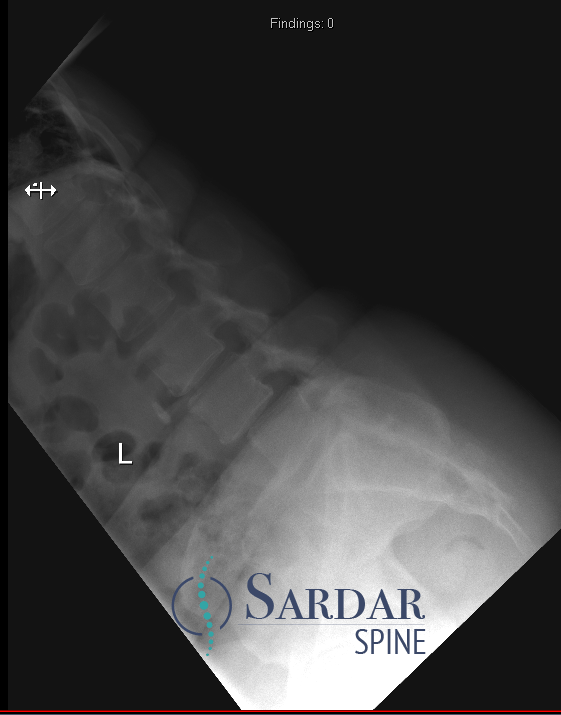

From robotics and AI-driven surgical planning to virtual modeling and custom implants, I’ve embraced a combination of tools that allow me to create tailored surgical plans for my patients—particularly those with scoliosis and spinal deformities.

What sets my approach apart is the seamless integration of these advanced technologies to ensure unparalleled accuracy and better outcomes for each patient.